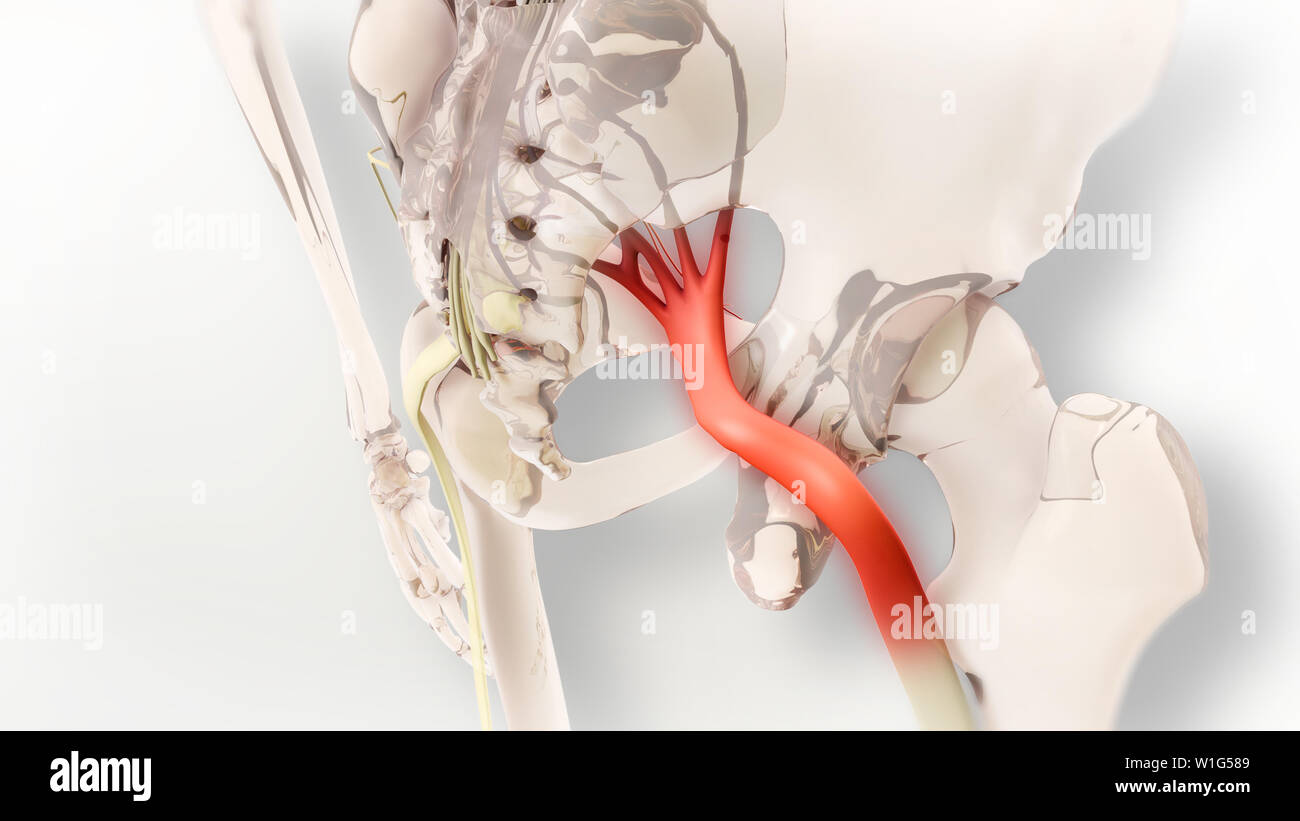

La douleur du nerf sciatique 3D Illustration Banque D'Imageshttps://www.alamyimages.fr/image-license-details/?v=1https://www.alamyimages.fr/la-douleur-du-nerf-sciatique-3d-illustration-image259125561.html

La douleur du nerf sciatique 3D Illustration Banque D'Imageshttps://www.alamyimages.fr/image-license-details/?v=1https://www.alamyimages.fr/la-douleur-du-nerf-sciatique-3d-illustration-image259125561.htmlRFW1G589–La douleur du nerf sciatique 3D Illustration